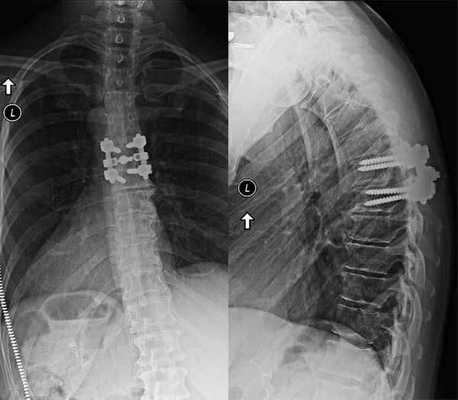

Если клиника симптомов не поддается консервативной терапии или неинвазивные способы не могут быть задействованными ввиду сильно прогрессирующего стеноза, назначается операция. Вмешательство предполагает использование декомпрессионной ламинэктомии под общим наркозом. При комбинированной проблеме, например, вместе с грыжей, ее сочетают с микродискэктомией и спондилодезом. При спондилодезе осуществляют скрепление смежных позвонков металлическими фиксаторами (стержнями, пластинами, крючками и пр.), установку межтеловых имплантатов или вживление костного трансплантата с металлической гильзой.

Установка металлической конструкции.